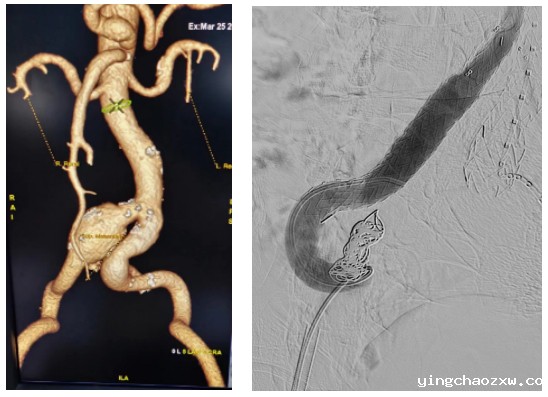

“步步常由逆境行,极知造物欲其成。”近日,新利官网登录北院区外二科、西院区骨伤科血管外科专业组白磊医生在云南省兴滇名医、昆明医科大学附属延安医院普外二科(血管外科)刘训强主任的指导下,充分发扬不畏艰险,迎难而上的仁医精神,成功完成我县首例经股动脉入路腹主动脉覆膜支架隔绝术,有力填补了新利官网登录在大血管疾病介入治疗领域的空白,标志着新利官网登录大血管疾病介入治疗技术迈上了新的台阶。

据悉,患者为男性,现年72岁。因腹部疼痛被家人送往省级医院诊治,经CTA检查(CT血管造影),被明确诊断为右髂总动脉瘤,后被家人送至新利官网登录西院区(新平县中医医院)进行治疗。由于患者髂总动脉瘤体积较大,已扩展至腹主动脉开口处,瘤体一旦破裂,血液就会奔涌而出,导致患者随时面临着死亡的威胁,形同体内被安放了一枚“定时炸弹”。为了帮助患者拆除这枚安放于体内的“定时炸弹”,让患者早日恢复健康,新利官网登录北院区外二科、西院区骨伤科血管外科专业组认真研究患者病情,制定了详细的诊疗计划,并决定在昆明市延安医院普外二科(血管外科)刘训强主任的指导下,为该患者实施局麻下经股动脉入路腹主动脉覆膜支架隔绝术。在血管外科专业组全体医务人员的不懈努力下,手术不到2个小时即告完成。术后患者恢复良好,目前已康复出院,患者及家属对本次治疗效果非常满意。

在传统的大动脉瘤治疗方式中,主要采取全身麻醉下开腹,再置换一根人工血管,手术创伤大,死亡率高。随着医疗器械和技术的进步,微创介入手术已经成为大动脉瘤治疗的首选。多数主动脉瘤在采用微创介入手术治疗期间,只需要在双侧大腿根部穿刺两个小口,通过股动脉将支架送入腹主动脉,将动脉瘤覆盖,即可达到治疗目的。相较于传统手术,微创介入手术治疗具有创伤小、治疗时间短、恢复快等优点,有效缩短了患者的住院时间,极大地减轻了患者的经济负担。